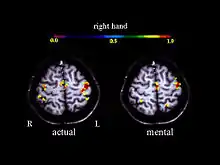

A large number of functional neuroimaging studies have demonstrated that motor imagery is associated with the specific activation of the neural circuits involved in the early stage of motor control (i.e., motor programming). This circuits includes the supplementary motor area, the primary motor cortex, the inferior parietal cortex, the basal ganglia, and the cerebellum.[21][22] Such physiological data gives strong support about common neural mechanisms of imagery and motor preparation.[23]